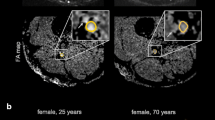

FA values from DTI20 as well as FApseudo values from models 1, 2, and 3 were clearly lower in diabetic patients than in young or age-matched controls (p < 0.001, Fig. 3b). ROC analysis revealed excellent discrimination between patients and age-matched controls by all models achieving comparable values of areas under the receiver operating characteristics curve of 0.847 (DTI20, p = 0.004), 0.854 (model 3, p = 0.003), 0.861 (model 1, p = 0.003), and 0.868 (model 2, p = 0.002; Fig. 3a). Furthermore, patients had increased ADC or ADCpseudo and RD or RDpseudo values compared to either control group (p < 0.001) in all models, while ADpseudo from models 1, 2, and 3 was only slightly higher in patients (p < 0.001 and p = 0.003; Supplementary Fig. S5). Figure 4 shows FA maps derived from DTI20 and models 1, 2, and 3 in a representative diabetic patient and healthy participant.

Fractional anisotropy (FA) map reconstructions in healthy and diabetic patients. Representative images of a healthy subject (a) and a diabetic patient (b) showing T2-weighted images of the distal sciatic nerve and corresponding color-coded fractional anisotropy (FA) maps calculated with the 20-directional standard model (DTI20) and the reduced models 1, 2, and 3. Segmentation of the nerve portion is indicated by a white contour. Insets show a magnification of the nerve. Model 1 achieves the best approximation to DTI20 in both healthy and diseased nerve tissue, while models 2 and 3 yield good but inferior accuracy

Regarding factors potentially influencing read-out parameters in a negative way, we found that smaller deviations of nerve angulation seemed to have a negligible effect on the accuracy of the simplified diffusion models. Similarly, the accuracy of the models was not found to be strongly affected by the amount of intraneural connective tissue. Instead, we found that absolute FA values decreased with more intraneural connective tissue in all models including the standard 20-vector model. Given the currently limited spatial resolution of diffusion sequences, this raises the question of whether partial volume effects may substantially contribute to the reduction of FA found in many peripheral neuropathies.